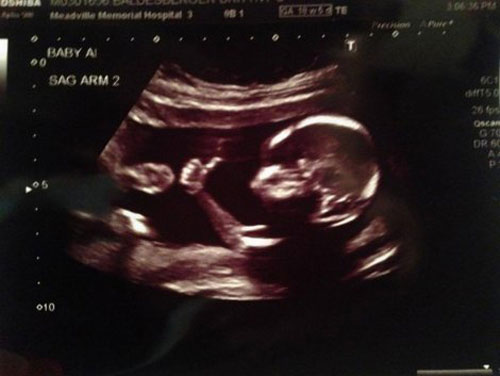

Една мајка останала без зборови кога го видела бебето на ултразвук, тоа го држело палецот нагоре, како да и кажува на мајка си дека се е во ред.

Откако таткото на бебето ја објави фотографијата на „Редит“, таа го обиколи целиот интернет.

– Ова дете е толку кул, а се уште не е родено – напишал еден корисник на интернет, додека други коментираат дека момчето сигурно ќе биде политичар или рок-ѕвезда.

Оние кои ја виделе сликата од ултразвукот, исто така, забележале дека ова бебе не е само. Мајката потврдила дека чека близнаци.